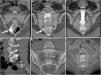

Spontaneous intracranial hypotension is an increasingly recognized cause of atypical, secondary headaches. Nevertheless, its clinical and imaging spectrum is far from an exhaustive definition, ranging from straightforward cases with unambiguous findings and prompt response to treatment to more challenging ones, requiring advanced, more complex imaging and targeted therapies. We describe two unusual cases as a cue to draw a literature-based, practical approach to the management of the syndrome.